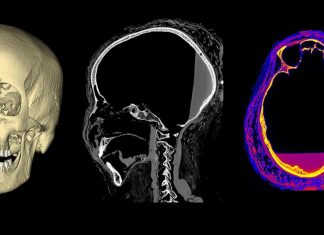

المرأة الحامل صاحبة المومياء الغامضة.. ربما ماتت بالسرطان

أفريقيا برس - السودان. أدرك الباحثون لأول مرة احتمال وجود سرطان بعد قيامهم بإعادة بناء ثلاثية الأبعاد لجمجمة السيدة الغامضة، التي كشفت عن ثقب...